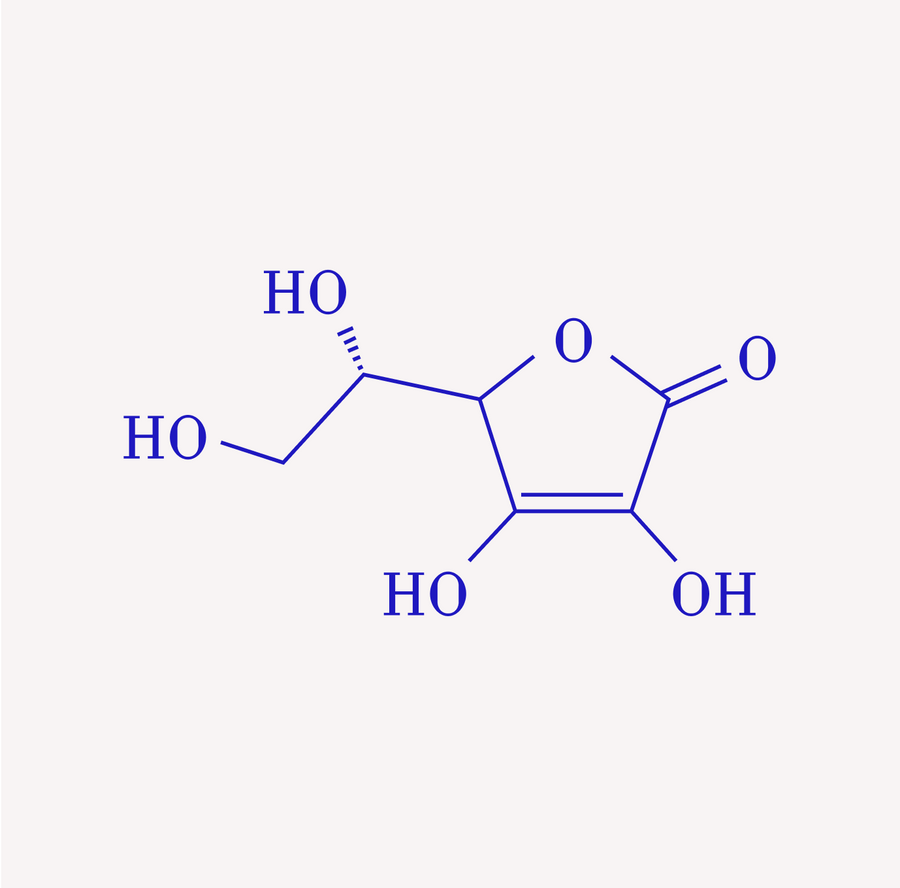

Vitamins C, D, K

Support immune defenses, cardiovascular, and bone health.

Vitamin C has a strong antioxidant effect, lightens pigment spots, and promotes collagen formation for an even complexion.

Vitamin C has a strong antioxidant effect, lightens pigment spots, and promotes collagen formation for an even complexion.

Jolliffe et al. Vitamin-D-Supplementierung zur Vorbeugung akuter Atemwegsinfektionen: eine systematische Überprüfung und Metaanalyse aggregierter Daten aus randomisierten kontrollierten Studien. The Lancet Diabetes & Endocrinology 2021

Richards JB, Valdes AM, Gardner JP, Paximadas D, Kimura M, Nessa A, Lu X, Surdulescu GL, Swaminathan R, Spector TD, Aviv A. Höhere Vitamin-D- Konzentrationen im Serum sind bei Frauen mit einer längeren Telomerlänge der Leukozyten verbunden. Am J Clin Nutr. 2007 Nov;

Anilkumar SA, Dutta S, Aboo S, Ismail A. Vitamin D als Modulator molekularer Signalwege bei Herz-Kreislauf-Erkrankungen: Belege aus präklinischen Studien. Life Sci. 15. November 2024; Grant WB, Wimalawansa SJ, Pludowski P, Cheng RZ. Vitamin D: Evidenzbasierter gesundheitlicher Nutzen und Empfehlungen für Bevölkerungsrichtlinien. Nährstoffe. 14. Januar 2025;

Haidong Zhu, JoAnn E Manson, Nancy R Cook, Bayu B Bekele, Li Chen, Kevin J Kane, Ying Huang, Wenjun Li, William Christen, I-Min Lee, Yanbin Dong, Vitamin D3 und marine ω-3-Fettsäuren-Supplementierung und Leukozyten- Telomerlänge: 4-Jahres-Ergebnisse aus der randomisierten kontrollierten Studie VITamin D and OmegA-3 TriaL (VITAL), The American Journal of Clinical Nutrition, 2025.

Montoya-Estrada A, García-Cortés AY, Romo-Yañez J, Ortiz-Luna GF, Arellano-Eguiluz A, Belmont-Gómez A, Lopéz-Ugalde V, León-Reyes G, Flores-Pliego A, Espejel-Nuñez A, Solis-Paredes JM, Reyes-Muñoz E. Die Verabreichung von Resveratrol und Vitamin C reduziert oxidativen Stress bei Frauen nach der Menopause – eine randomisierte klinische Pilotstudie. Nährstoffe. 3. Nov. 2024;

Chen et al. Orales Nicotinamid reduziert den transepidermalen Wasserverlust: eine randomisierte kontrollierte Studie. British Journal of Dermatology 2016